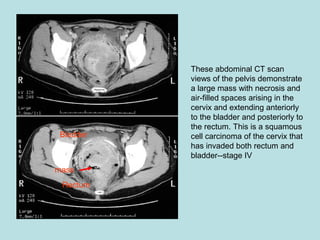

These abdominal CT scan

views of the pelvis demonstrate

a large mass with necrosis and

air-filled spaces arising in the

cervix and extending anteriorly

to the bladder and posteriorly to

the rectum. This is a squamous

cell carcinoma of the cervix that

has invaded both rectum and

bladder--stage IV

mass

Bladder

Rectum